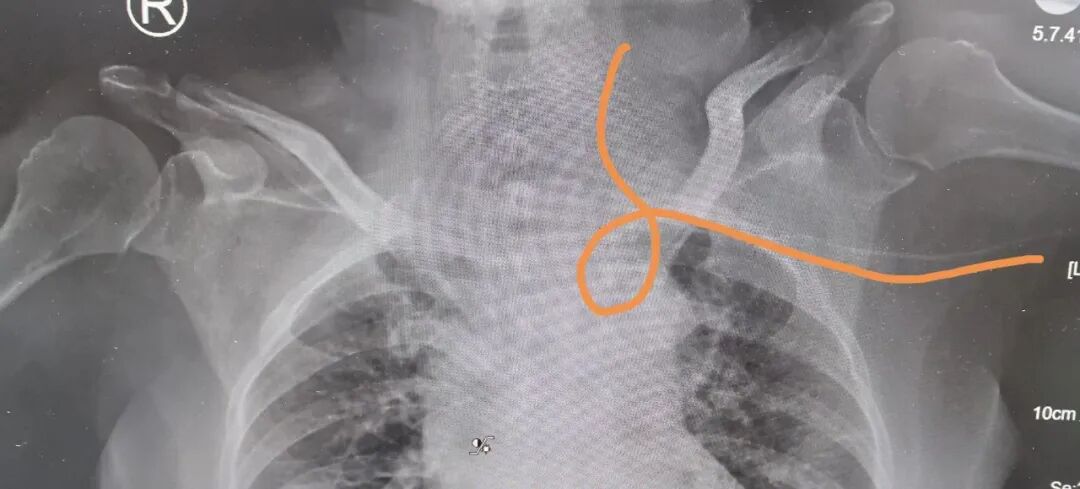

院外带入导管异位

导管再次异位